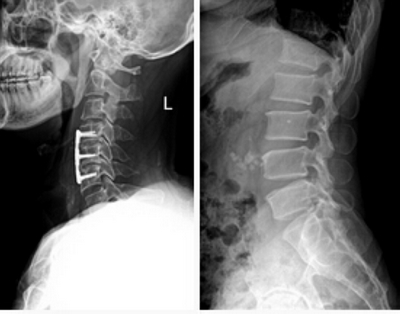

★適用于全身各部位攝影,包括常規攝影(立位攝影、臥位攝影等,如胸片、頸椎、腰椎、腹部、頭顱、四肢等)和特殊攝影(傾斜攝影、角度攝影等,如瓦氏位、骶髂關節、髕骨軸位、跟骨軸位等)。